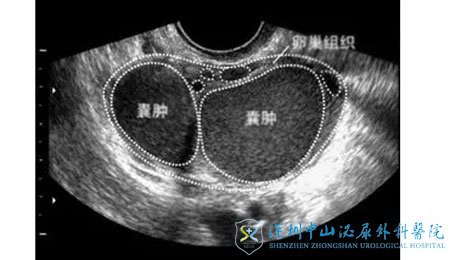

子宫内膜跑到了卵巢组织中,在卵巢中周期性出血,使得卵巢会不断增大而形成囊肿,这就是巧克力囊肿的由来。

患上巧克力囊肿后,具有双侧性、囊壁厚的特点。囊肿会与周围的组织紧密相连,在每次月经周期时,囊腔内部会有较多的出血,囊肿会扩大,囊液是褐色的,与巧克力液同样的颜色,为陈旧性出血。